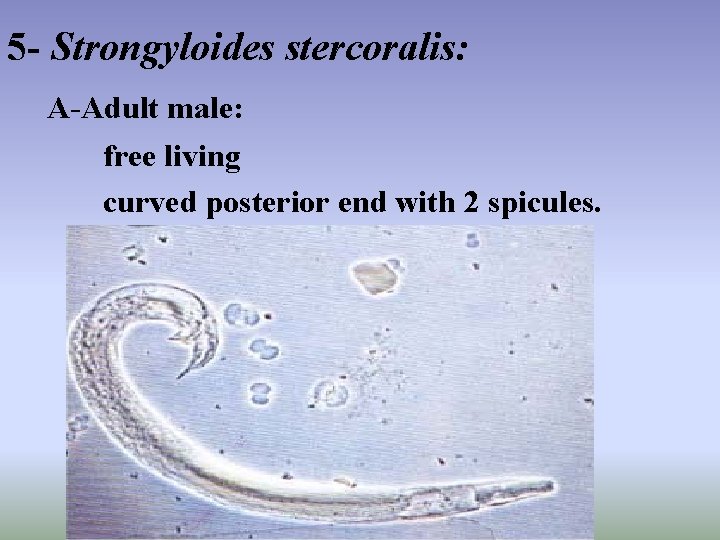

5 - Strongyloides stercoralis: A-Adult male: free living curved posterior end with 2 spicules.